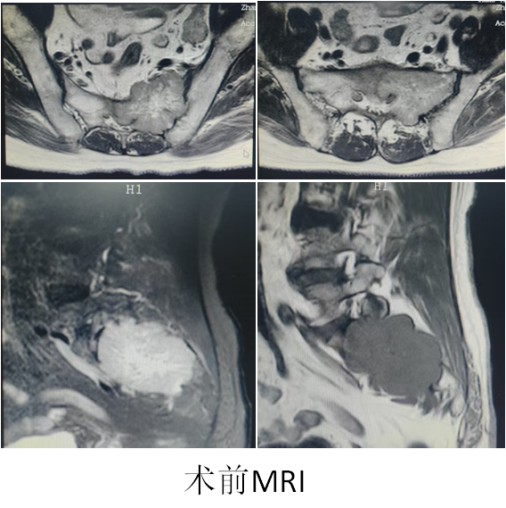

近日,一位高龄患者张某因骶部剧烈疼痛前来我院就诊,经检查发现其骶2水平左侧有一巨大肿瘤。患者左侧臀部疼痛剧烈,口服及注射止痛药均难以控制。更为复杂的是,两周前患者突发脑梗,累及语言中枢,导致语言功能严重受损,日常交流极其困难。由于肿瘤位置深,紧邻重要神经血管结构,多家医院均因病情复杂而未能收治。

综合评估后,骨肿瘤外科中心团队决定采用机器人辅助导航技术,施行经皮穿刺活检(以明确肿瘤性质及基因测序,为后续靶向治疗提供依据)联合肿瘤冷热复合消融术,实现姑息性肿瘤灭活,从而缓解剧烈疼痛,并为明确诊断及后续治疗争取机会。该手术在局部麻醉下实施,不仅减轻全麻对机体的影响,降低脑梗再发风险,也避免了椎管内麻醉的不确定性及肿瘤椎管内扩散的潜在风险;局部麻醉同时还有效缓解了患者的癌痛,并且术中还能观察有无神经根性损伤等表现,为高风险条件下的治疗提供了新思路。

9月6日,在机器人系统精准引导下,骨肿瘤外科中心团队将一根纤细的穿刺针经皮穿刺至骶骨深部肿瘤中心,取材后经同一通道进行消融治疗。手术全程在局麻下进行,患者始终保持清醒。肿瘤组织经历两次“冷冻(-195℃持续15分钟)-复温-加热(85℃,持续5分钟)”循环后被彻底毁损,邻近重要神经、血管在实时监控下得到最大程度保护。术中即刻复查CT显示肿瘤消融范围充分,达到预期灭活效果,整个过程出血不足10ml。